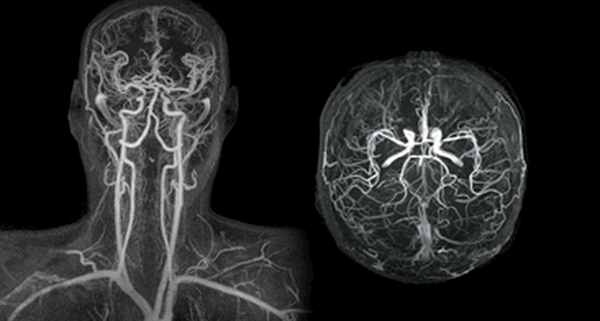

3D-реконструкция артерий шеи при КТА

КТ-ангиография сосудов шеи визуализирует артерии и вены брахиоцефального бассейна. С помощью специальной компьютерной программы, позволяющей придать изображениям объем, рентгенолог видит притоки и мелкие коллатерали, внутренние причины нарушения кровотока, патологические процессы в близлежащих тканях и органах, оказывающие компрессионное действие на артерии и вены. Что показывает КТ сосудов шеи:

На томограммах четко прослеживается архитектоника сосудов исследуемой области

КТ-ангиография сосудов шеи с контрастом незаменима при травмах: скорость получения результата и отличная визуализация сосудистых катастроф, повреждений костных структур и нервных тканей позволяют быстро определить тактику ведения пациента. Большинство патологических процессов протекают генерализованно (атеросклероз, аутоиммунные заболевания), поэтому необходимо исследовать одновременно сосуды головы и шеи на предмет характера поражения и степени выраженности заболевания. На томограммах можно увидеть:

КТ-ангиограмма кровеносных сосудов в области шеи. Позвоночная артерия находится между вертикальными линиями. Стрелка указывает на позвоночник

3D-изображения компьютерной мультиспиральной томографии Виллизиева круга. Его контуры можно увидеть на томограмме в центре, шея внизу, основные артерии белого цвета.